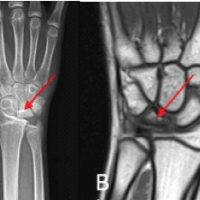

The patient was a 25-year-old married male at the time of the accident. He was working in an office (indoor) as an assistant manager in a government firm. He had an unusual mechanism of injury when he slipped from his two-wheeler in rain and hit his left side of the body to a tree. The patient sustained an injury of left hip joint and was admitted in a hospital at his hometown where initial evaluation, and first aid treatment was done. The patient came to our hospital 4 days after injury. A pelvic radiograph showed a Pipkin type III fracture (Fig. 1a). Trauma series radiographs of the patient ruled out fractures of other parts of the body. There was no comorbidity. Computed tomography revealed that the femoral head split into two parts almost vertically in a sagittal plane one fragment was lying posterior and the other one is in the joint. The associated femoral neck fracture was displaced anteriorly, sub-capital, and has irregular fracture line rotated externally. Tosounidis et al. [2] observed that in these injuries, the femoral neck fracture is always of vertical or irregular configuration and always displaced (Fig. 1c, 1d).